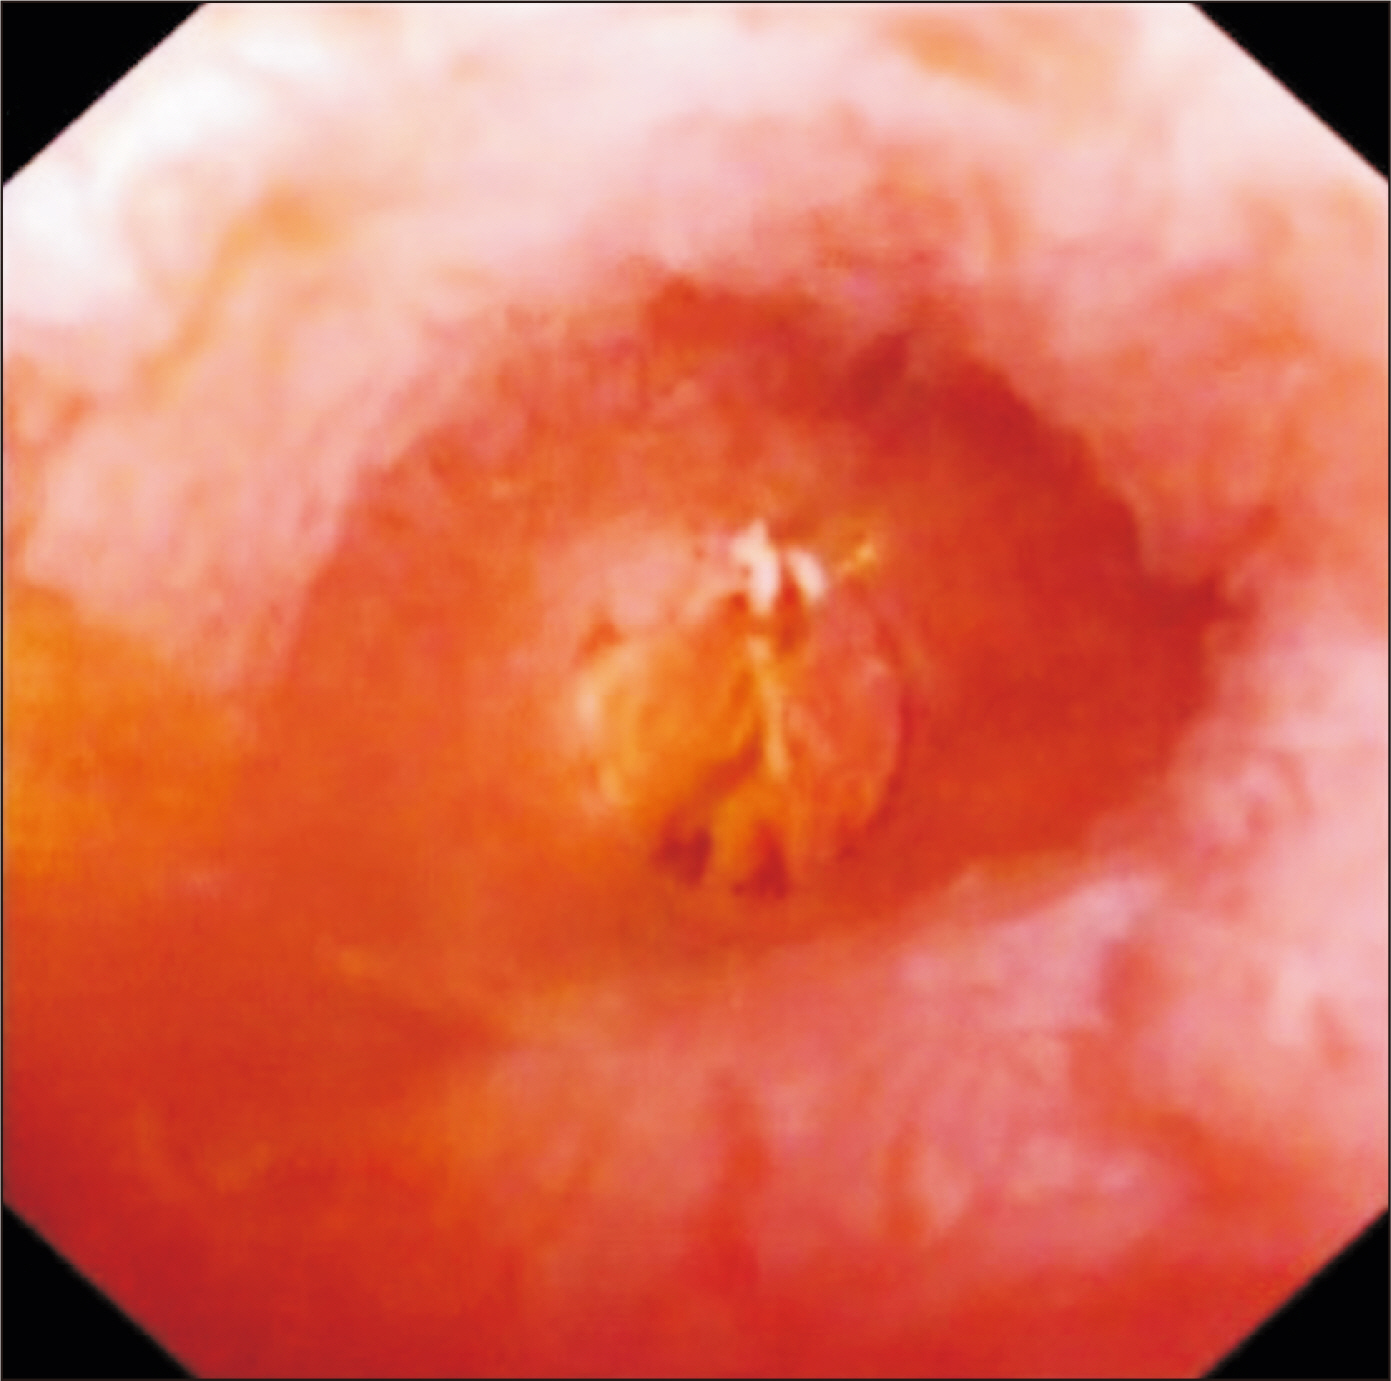

- Laparoscopic subtotal cholecystectomy (LSC) has been a safe and viable alternative to conversion to laparotomy in cases of severe cholecystitis. The objective of this study is to determine the utility of intraoperative choledochoscopy in LSC for the exploration of the gallbladder, cyst duct, and subsequent stone clearance of the cystic duct in cases of severe cholecystitis. A total of 72 patients diagnosed with severe cholecystitis received choledochoscopy-assisted laparoscopic subtotal cholecystectomy (CALSC). A choledochoscopy was performed to explore the gallbladder cavity and/or cystic duct, and to extract stones using a range of techniques. The clinical records, including the operative records and outcomes, were subjected to analysis. No LSC was converted to open surgery, and no bile duct or vascular injuries were sustained. All stones within the cystic duct were removed by a combination of techniques, including high-frequency needle knife electrotomy, basket, and electrohydraulic lithotripsy. A follow-up examination revealed the absence of residual bile duct stones, with the exception of one common bile duct stone, which was extracted via endoscopic retrograde cholangiopancreatography. In certain special cases, CALSC may prove to be an efficacious treatment for the management of severe cholecystitis. This technique allows for optimal comprehension of the situation within the gallbladder cavity and cystic duct, facilitating the removal of stones from the cystic duct and reducing the residue of the non-functional gallbladder remnant.

Figure